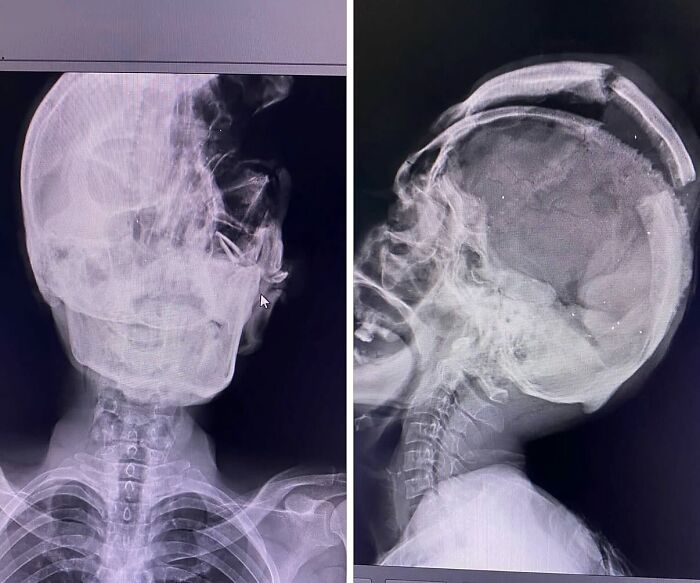

Extreme Case Of Hydrocephalus In A Pediatric Patient

Hydrocephalus is a pathology characterized by dilation of the cerebral ventricles, normally caused by the obstruction of the flow of cerebrospinal fluid (CSF), or by an imbalance between its production and absorption, in addition there is inflammatory response, neuronal damage and destruction of periventricular axons.

Hydrocephalus is cataloged in two ways. Depending on the origin, it can be congenital or acquired; and in relation to the CSF flow, this pathology is classified as communicating (i.e. CSF can exit the ventricular system, but the fluid is not absorbed readily, or there is too much fluid to be absorbed) or non-communicating (i.e. CSF cannot exit the ventricular system, and thus there is obstruction to CSF absorption, resulting in an increased pressure inside the brain). Symptoms of hydrocephalus may include an unusually large head with thin, transparent scalp, bulging forehead with increased spaces between the bones of the skull (fontanelles), and a downward gaze.

The most common congenital cause is the obstruction or narrowing (stenosis) of the cerebral aqueduct — the long, narrow passageway between the third and fourth ventricles of the brain. It can also be caused by infections, hemorrhage or a tumor.

The condition is pretty rare and can be easily detected early in pregnancy by ultrasound which does not necessarily shows the obstruction but detects an abnormal collection of fluid.

These kids are treated after birth by either inserting a shunt, small flexible plastic tube that diverts excess CSF from the brain to another part of the body where the fluid can be reabsorbed; or by an endoscopic ventriculostomy, where a small hole is made in the floor of the third ventricle, allowing the CSF to bypass the obstruction and flow toward other areas where reabsorption can happen.